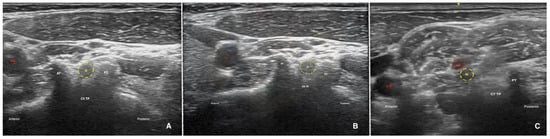

2.4.2. CSNRB Group